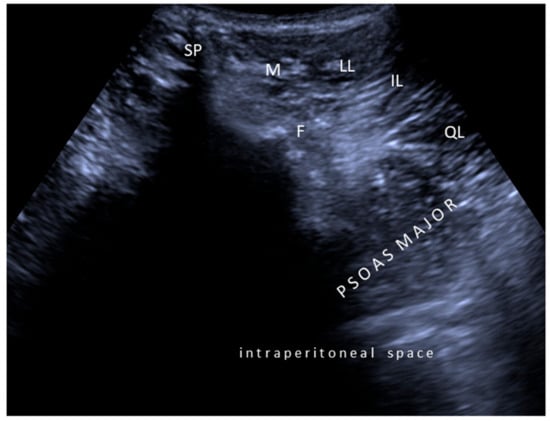

Second, concerning particular muscles, we strongly disagree with the authors regarding tibialis posterior, iliopsoas, and sternocleidomastoid injections. In the former two muscles, the innervation zones are well known to be localized much more proximal [,,], necessitating injections accordingly (Figure 1 and Figure 2). For the latter one, again based on the evidence of innervation zone distribution, latero-medial rather than cranio-caudal injection would be crucial (Video 1). Yet, the innervation zones are shown to be arranged perpendicular to the muscle fibers [].

Figure 1.

Ultrasound imaging (axial view) for psoas major muscle. SP: Spinous process; F: Facet joint; M: Multifidus; LL: Longissimus lumborum; IL: Iliocostalis lumborum; QL: Quadratus lumborum.